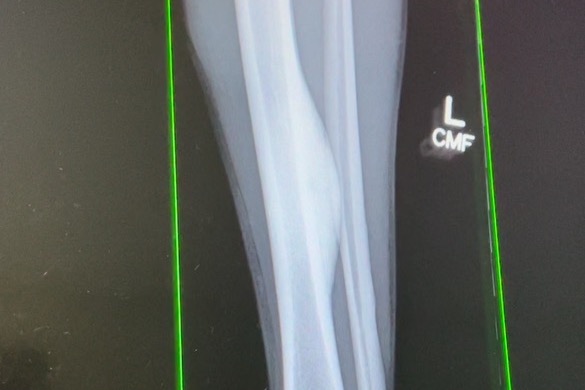

Last week doctors found a tumor growing between the bones in Zach’s leg. The tumor continues to grow and is currently causing nerve entrapment (pinched nerve) to the sciatic nerve. This has caused him to lose 50% of the nerve function in his leg, resulting in excruciating pain and the inability to walk. The tumor needs to be removed as soon as possible and we anticipate lots of medical expenses, from MRI’s to surgery to recovery in the hospital.